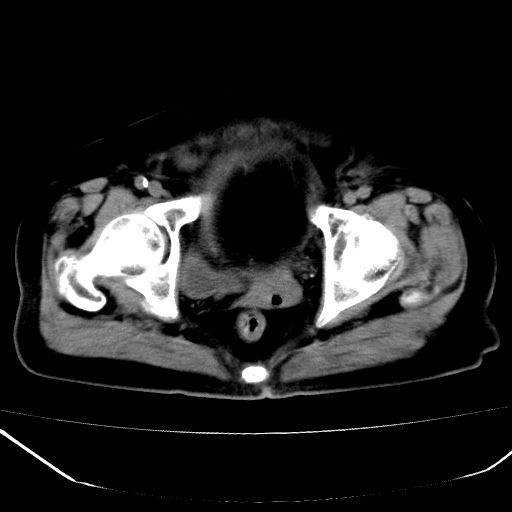

患者,女,74岁,无不适,b超示盆腔包块。

子宫前上方巨大脂性肿物,肿物边缘为较厚软组织密度影,其内缘欠光整,脂性密度中央见结节状软组织密度影“漂浮”,肿物与子宫前壁关系密切,考虑1脂肪瘤2皮样囊肿3肌瘤脂样变

膀胱是?

ct值-90hu